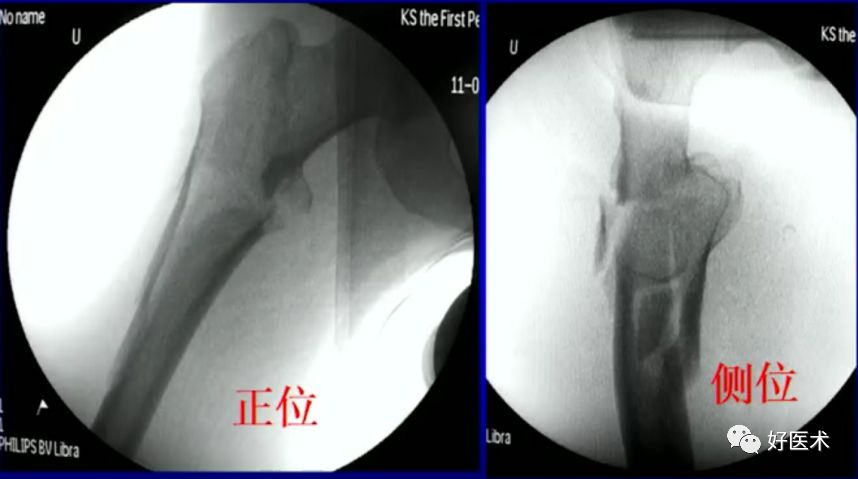

6.正确的股骨颈正侧位

侧卧位如何透股骨颈的侧位:

-

标准侧位

球管20-30°

侧卧位行转子间骨折固定

病例:男,34岁,高处坠落伤,仅骨折余正常